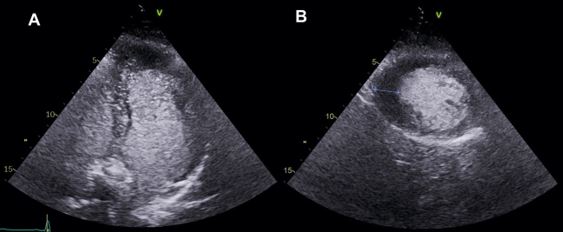

- Apical ventricular hypertrophy: less common in general. It is characterised by hypertrophy of the apical segments and a resultant “ace of spades” diastolic LV cavity in the apical 4-chamber axis. The diagnosis may be missed when the apical endocardium is not well visualised, and in these cases, CE unveils the diagnosis (Figure 2).